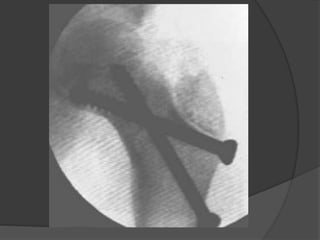

• 8.

Evaluación radiológica  Rxanteroposterior y proyección cruzada de la cadera afecta  TAC y RMN  Gammagrafía, después de las 48hs

Clasificación Delbet - ColonnaTipo I: transepifisiaria A: No luxada B: luxada  Tipo II: transcervical  Tipo III: basecervical  TipoIV: Intertrocanterica

Tipo 1  Menosfrecuente  Incidencia del 8% de las fracturas del cuello  Presentan necrosis avascular en el 70% de los casos  Mejor pronostico en menores de 2-3 años

Tipo 2  Representanel 46% de los casos  77% desplazadas  Se presenta necrosis avascular en el 45-50% de los casos  Necrosis avascular directamente proporcional al desplazamiento

Tipo 3  Ocupael segundo lugar de frecuencia  Incidencia del 34%  Presentan necrosis avascular en el 30% de los casos  Riesgo de necrosis avascular directamente proporcional al desplazamiento  Cierre prematuro de la fisis en 25%

Tipo 4  Representanel 12% de las fracturas  Presenta menor índice de complicaciones